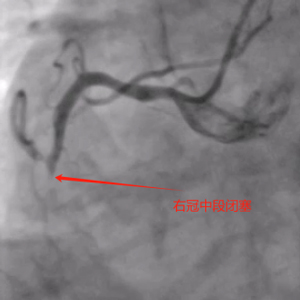

造影可见:前降支中段发出对角支后极重度狭窄,可见侧支循环右冠中远端,回旋支发出钝缘支后闭塞,可见钝缘支侧支循环回旋支远端;右冠中段闭塞。

11月5日,患者各方面情况相对稳定,口服双联抗血小板聚集药物消化道反应也无异常。综合评估后再次为患者行冠脉介入治疗。术前我把老吴左右手都消毒了,左手备用,可能需要双侧造影辅助开通右冠。术中顺利开通右冠闭塞血管并植入支架恢复正常血流,同期解决前降支极重度狭窄病变并植入支架解除危机。手术总用时1小时40分钟,造影剂用量120ml,手术很顺利,比预想的效果要好,已经超预期完成。